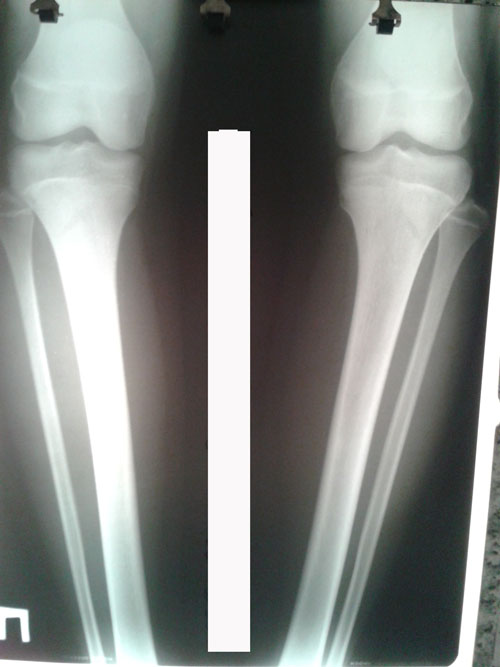

Исходник - 13 лет.

Дата операции 02.06.2016г.

У пациентки двухсторонняя ротация.

Дата снятия аппаратов 27.07.2016г.

Срок лечения 55 дней.